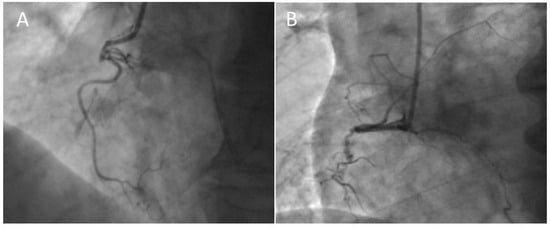

4.4. Retrograde Recanalization

4.4.3. Externalization of the Guidewire